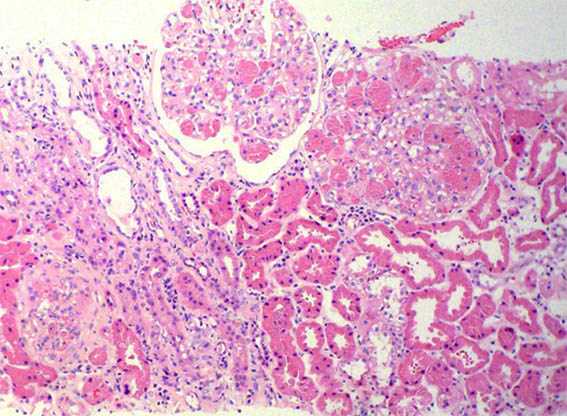

Se hace biopsia renal, observe las imágenes.

Figura 1. H&E, X100.